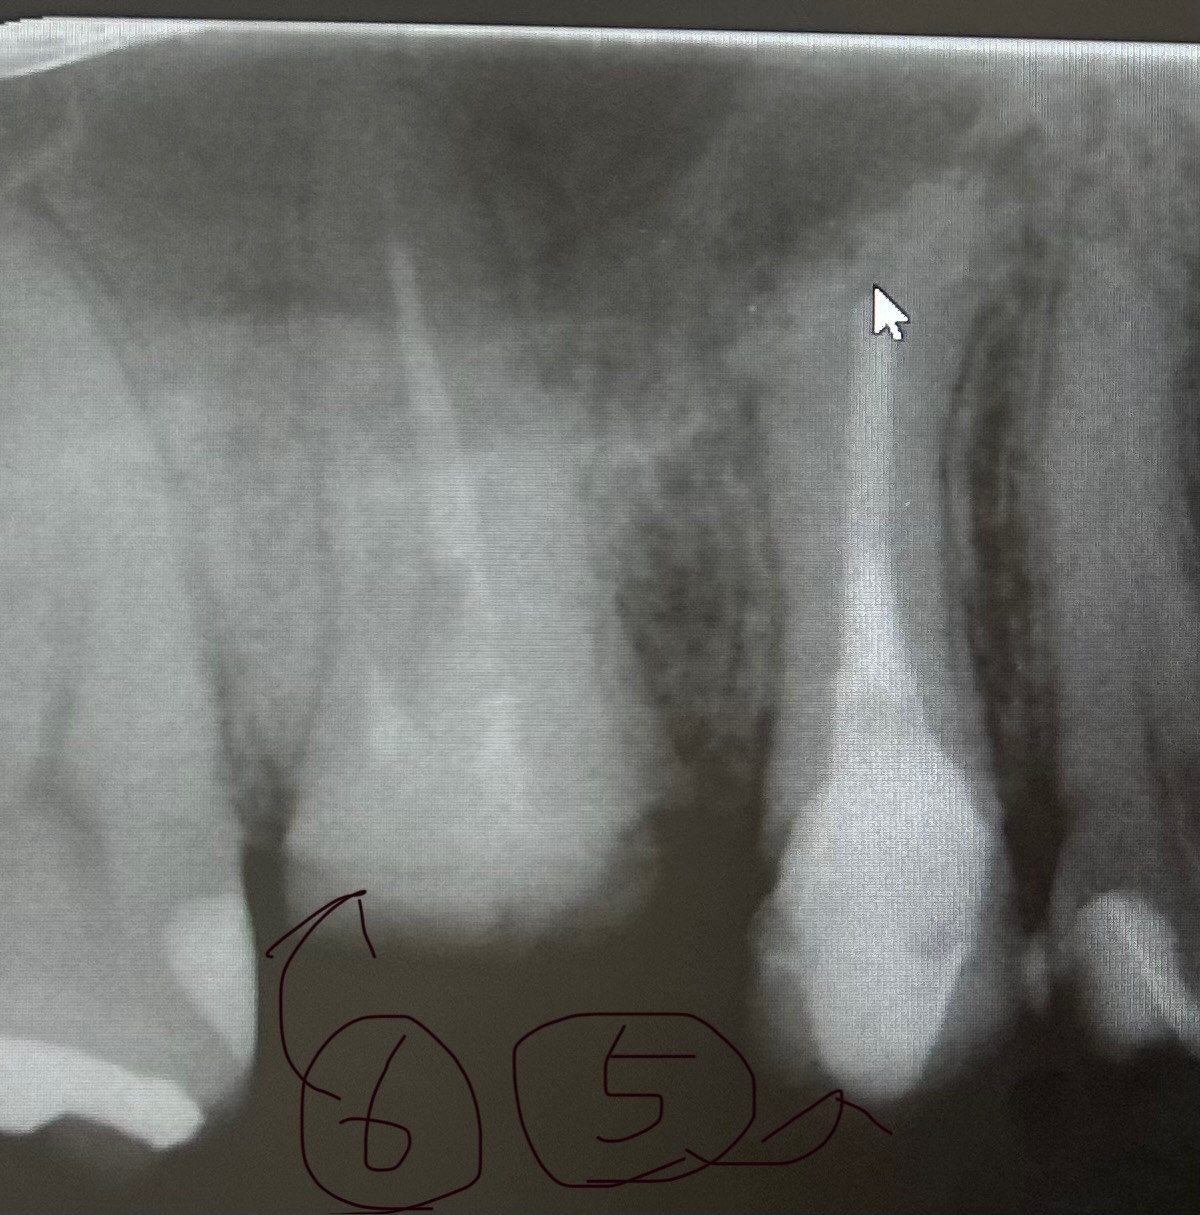

しかし、なんとなく、治療がはじまってから、5番の方が疼いている感じがして、気になってます。大学病院の、歯科に紹介されて小さいレントゲンにて、5番は下までちゃんと薬も入ってるし大丈夫でしょう。と言われましたが、歯の先がモヤモヤしているところがあり、気になります。6番も、固くて奥までなかなか進めないらしく、難航しています。

もう、この5番の歯(矢印の方)は、抜歯すべきなのかと思ったのですが、どう思われますか。

画像1